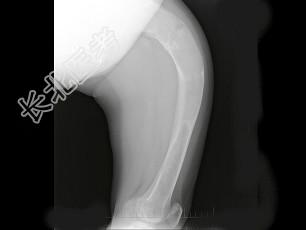

- 单项选择题男,17岁, 下肢畸形,有皮肤色素沉着, 性早熟等,结合图像, 最可能的诊断是 ( )

C、骨纤维结构不良